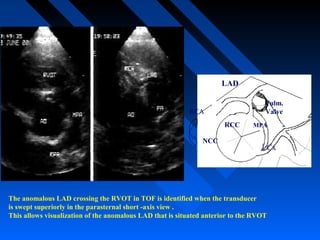

LAD

RCC

NCC

RCA

LCx

Pulm.

Valve

MPA

The anomalous LAD crossing the RVOT in TOF is identified when the transducer

is swept superiorly in the parasternal short -axis view .

This allows visualization of the anomalous LAD that is situated anterior to the RVOT

LAD RCC NCC RCA LCx Pulm. Valve MPA The anomalous LADcrossing the RVOT in TOF is identified when the transducer is swept superiorly in the parasternal short -axis view . This allows visualization of the anomalous LAD that is situated anterior to the RVOT